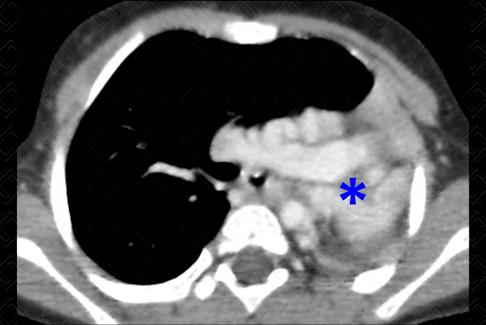

Descrição das figuras 1 e 2: Paciente com 2 anos, realizou radiografia de tórax na emergência. Observou-se a presença de hemitórax opaco, com o lado acometido de dimensões reduzidas. A equipe da radiologia optou por complementar estudo com tomografia do tórax após a administração do contraste venoso. Foi evidenciado brônquio fonte esquerdo, que termina em fundo cego (seta vermelha) e a não existência da artéria pulmonar esquerda (asterisco), compatível com diagnóstico de aplasia pulmonar. Não há evidências de parênquima pulmonar esquerdo, com desvio ipsilateral do mediastino.

Aplasia pulmonar: Faz parte do espectro de anomalias do parênquima e circulação pulmonares. O espectro inclui agenesia, aplasia e hipoplasia pulmonar. Na aplasia pulmonar, nota-se a presença de um brônquio que termina em fundo cego, de aspecto rudimentar, sem evidência de vascularização ou parênquima pulmonar. [cms-watermark]

É importante diferenciar a agenesia de outras condições semelhantes, como aplasia e hipoplasia pulmonares. Na aplasia pulmonar, nota-se a presença de um brônquio que termina em fundo cego, de aspecto rudimentar, sem evidência de vascularização ou parênquima pulmonar. Os achados de imagem na radiografia de tórax são muito semelhantes à agenesia. O grande papel da TC de tórax é identificar o brônquio rudimentar.

Exames de imagem: A tomografia computadorizada do tórax é o exame de imagem de escolha para a avaliação dessas anomalias. Sempre realizá-la com contraste venoso para adequada avaliação da circulação pulmonar (figuras acima).